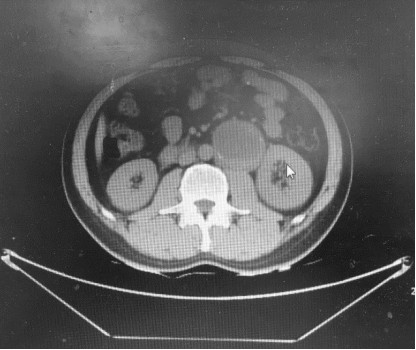

患者,男性,49岁,因体检行腹部彩超显示腹主动脉瘤,伴腰腹部困胀,无寒战、高热,恶心、呕吐,无腹痛、腹胀,无胸闷、气短,无便秘、腹泻等症状。一周后,患者收治于我院血管外科。入院后完善相关检查,进行CTA后显示腹主动脉左旁可见一类圆形低密度占位,大小约6cm病灶主体呈囊性,神经鞘瘤囊变可能,之后患者转入肿瘤外科。

图1 红色圈标记处为肿瘤